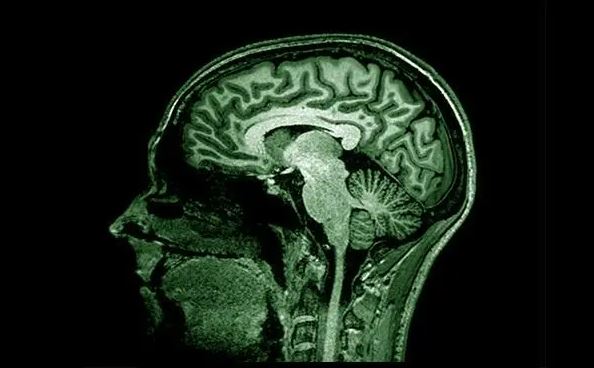

Nuevos avances para detectar el alzhéimer

El alzhéimer es una enfermedad neurodegenerativa que, según la Organización Mundial de la Salud (OMS), afecta a aproximadamente a 50 millones de personas a nivel mundial por lo que sus avances suponen uno de los grandes desafíos para la medicina moderna.